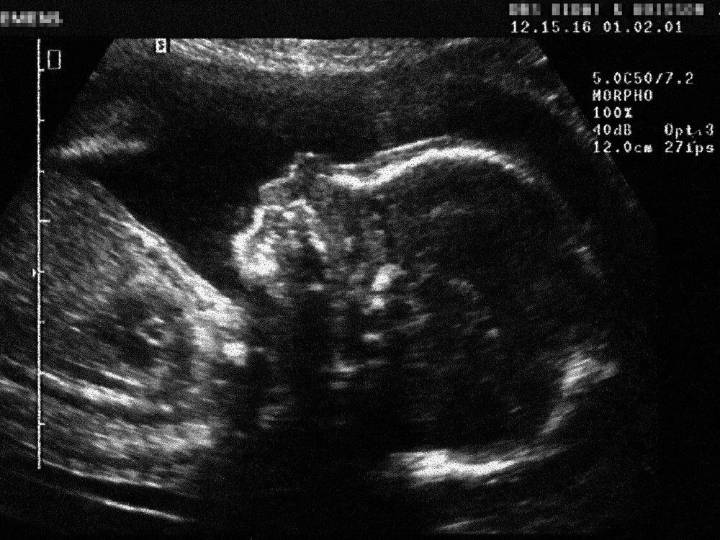

In 2013, former longtime Liberal MP Dr. Carolyn Bennett, in a terse letter to the National Post , said no doctor in Canada can terminate a pregnancy after 24 weeks unless the mother’s life is at risk or the fetus has serious complications.

“The assertion that late-term abortions can be performed ‘for any reason, or no reason at all’ is just not true,” wrote Bennett, who challenged a columnist to find a single late-term abortion performed in Canada “to a healthy mother with a healthy fetus.”

In fact, there need not be a medical reason for later gestational age abortion in Canada, according to Abortion Care Canada, formerly the National Abortion Federation of Canada.

“There does not have to be a specific medical concern that is named” to get an abortion beyond the fi